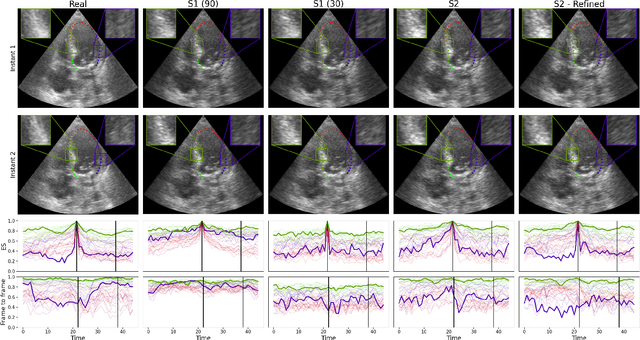

Abstract:Domain adaptation methods aim to bridge the gap between datasets by enabling knowledge transfer across domains, reducing the need for additional expert annotations. However, many approaches struggle with reliability in the target domain, an issue particularly critical in medical image segmentation, where accuracy and anatomical validity are essential. This challenge is further exacerbated in spatio-temporal data, where the lack of temporal consistency can significantly degrade segmentation quality, and particularly in echocardiography, where the presence of artifacts and noise can further hinder segmentation performance. To address these issues, we present RL4Seg3D, an unsupervised domain adaptation framework for 2D + time echocardiography segmentation. RL4Seg3D integrates novel reward functions and a fusion scheme to enhance key landmark precision in its segmentations while processing full-sized input videos. By leveraging reinforcement learning for image segmentation, our approach improves accuracy, anatomical validity, and temporal consistency while also providing, as a beneficial side effect, a robust uncertainty estimator, which can be used at test time to further enhance segmentation performance. We demonstrate the effectiveness of our framework on over 30,000 echocardiographic videos, showing that it outperforms standard domain adaptation techniques without the need for any labels on the target domain. Code is available at https://github.com/arnaudjudge/RL4Seg3D.

Abstract:Performance of deep learning segmentation models is significantly challenged in its transferability across different medical imaging domains, particularly when aiming to adapt these models to a target domain with insufficient annotated data for effective fine-tuning. While existing domain adaptation (DA) methods propose strategies to alleviate this problem, these methods do not explicitly incorporate human-verified segmentation priors, compromising the potential of a model to produce anatomically plausible segmentations. We introduce RL4Seg, an innovative reinforcement learning framework that reduces the need to otherwise incorporate large expertly annotated datasets in the target domain, and eliminates the need for lengthy manual human review. Using a target dataset of 10,000 unannotated 2D echocardiographic images, RL4Seg not only outperforms existing state-of-the-art DA methods in accuracy but also achieves 99% anatomical validity on a subset of 220 expert-validated subjects from the target domain. Furthermore, our framework's reward network offers uncertainty estimates comparable with dedicated state-of-the-art uncertainty methods, demonstrating the utility and effectiveness of RL4Seg in overcoming domain adaptation challenges in medical image segmentation.